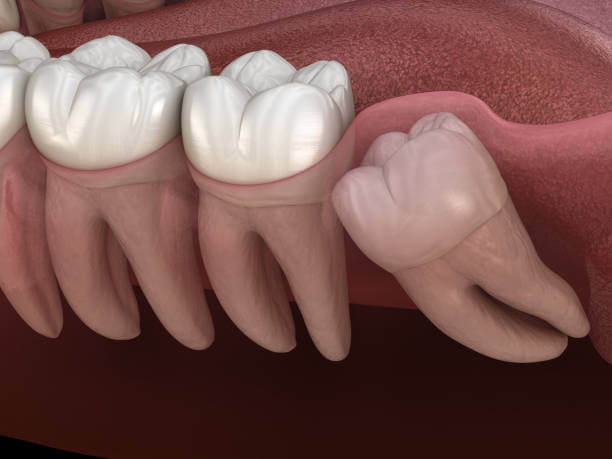

인류의 턱이 작아지면서 입안 깊숙이 사랑니가 자랄 공간이 부족해졌고 이 때문에 사랑니는 눕거나 발치하는 등 썩거나 염증이 생기기 쉬운 모양으로 나오는 경우가 많습니다.

사랑니는 다른 치아에 비해 크기와 모양이 매우 다양합니다. 사랑니는 똑바로 나오지 않고 기울어져 있거나 누워있는 경우 잇몸에 묻혀 있는 부분이 많습니다.

이 때문에 음식물 찌꺼기가 잇몸과 사랑니 사이에 끼기 쉽고 칫솔이 사랑니에 잘 닿지 않아 썩는 경우가 많고 제대로 청소하지 않으면 세균이 번식하고 염증이 생기기 쉬운 상태가 됩니다.

잇몸이 부어 오르거나 아플 때 감염이 느껴지고 위턱에 있는 사랑니가 부은 잇몸을 씹으면 더 불편 해집니다. 충치는 사랑니와 사랑니 앞 치아의 뒷면에도 형성될 수 있습니다. 이러한 충치는 종종 과소 검사되며 치통이 있을 때 가장 자주 발견됩니다. 심하면 양쪽 치아를 모두 뽑아야 하는 경우도 있습니다.

사랑니 주변에 염증이 생기면 잇몸이 붓고 볼이 붓고 침이나 음식을 삼키기 어려워지며 두통이 생깁니다. 목이나 턱뼈 안쪽으로 퍼지는 경우가 많아 입을 벌리기 어렵고 때로는 입원이 필요할 정도로 심한 사람들이 많습니다.